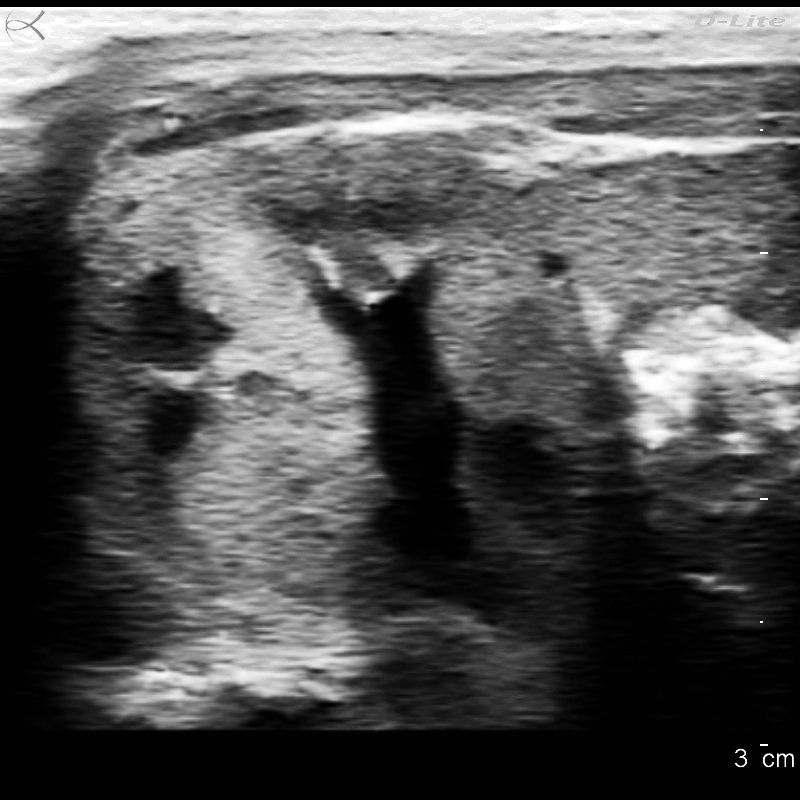

Ultrasound detects more invasive cancers, but number of total cancers detected is comparable between US and mammography.

Radiologists viewing supplemental breast ultrasounds should assess lesions separately to reduce the risk of missing a cancer.